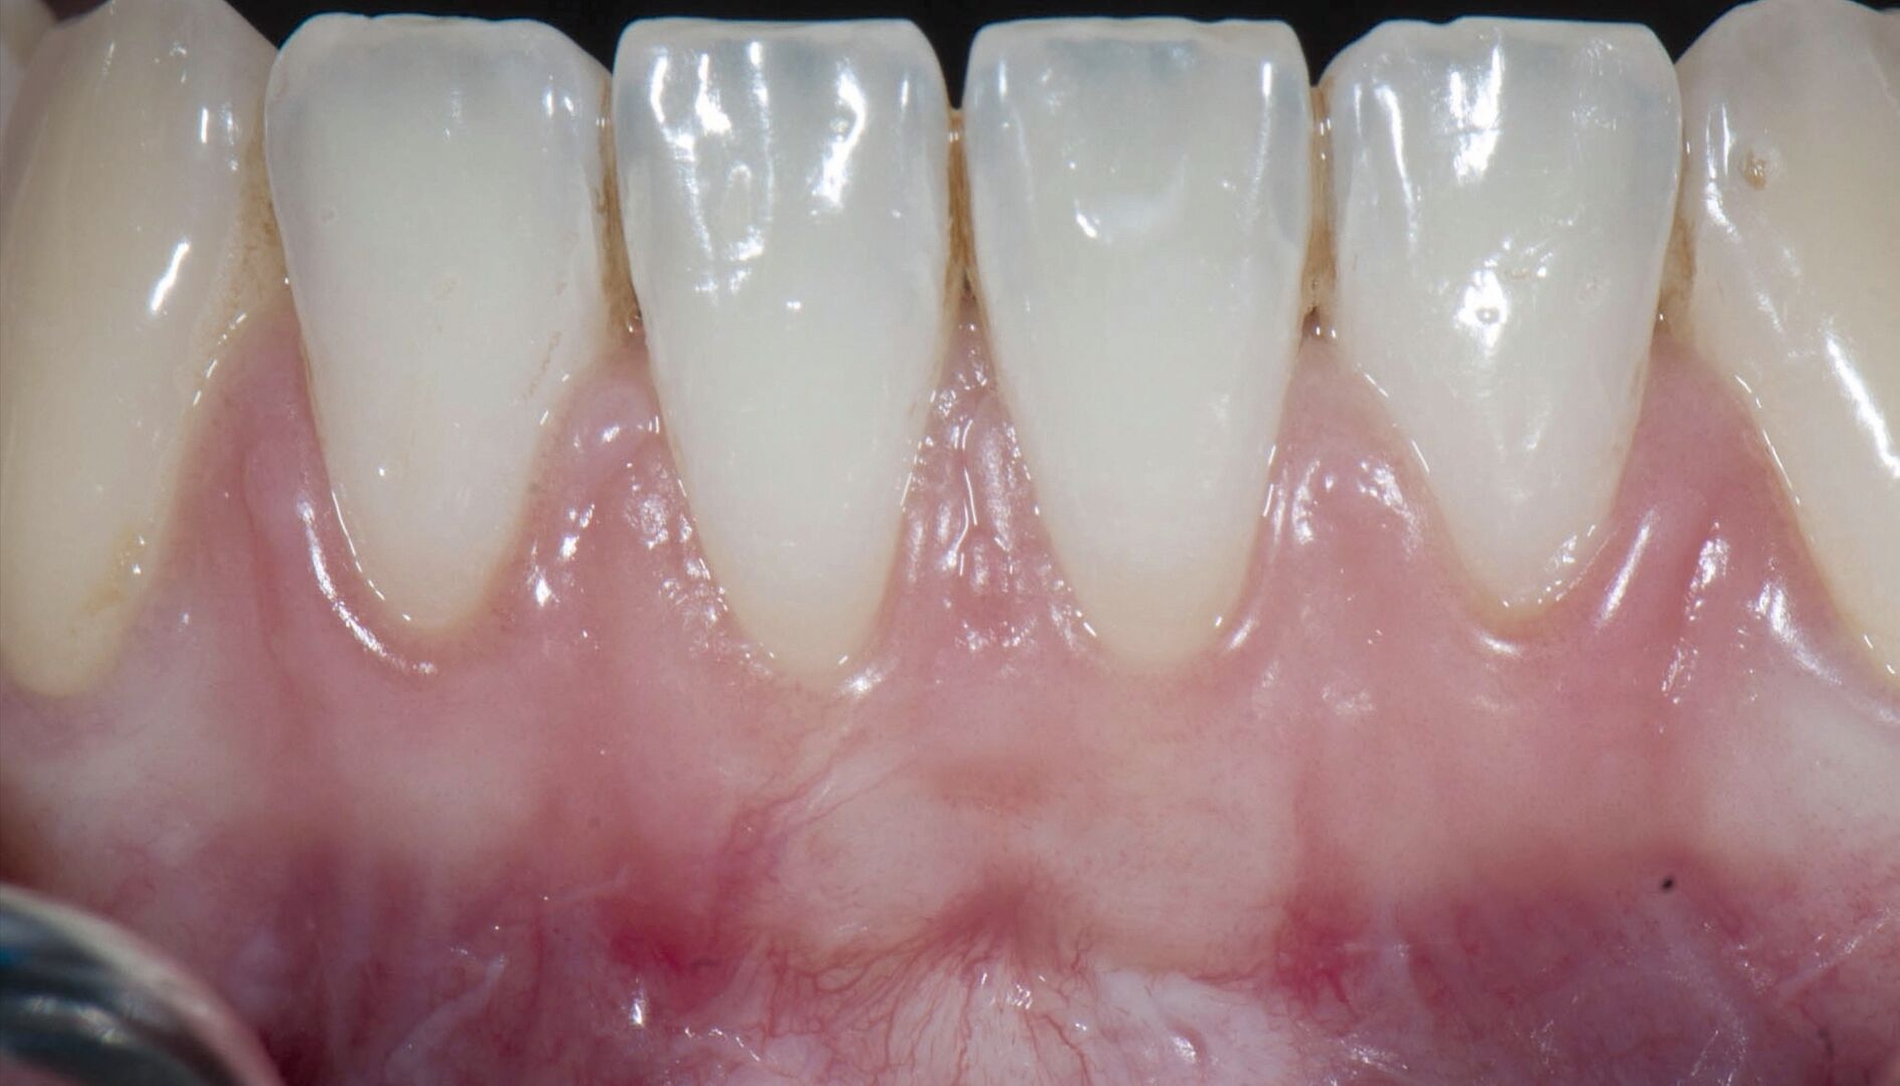

Im Ergebnis der Metaanalyse betrug die Reduktion der DH (ausgedrückt als prozentualer Anteil der Patienten, die initial von DH betroffen und nach der chirurgischen Wurzeldeckung davon befreit waren) 70,8 Prozent. Univariate Meta-Regressionen zeigten, dass sowohl das Ausmaß der Reduktion der Rezession (mm) als auch der Wurzeldeckung (Prozent) statistisch signifikant mit der Beseitigung der DH assoziiert waren. Hingegen zeigten der Zugewinn an Breite und Dicke der keratinisierten Gewebe keine signifikante Assoziation mit dem Rückgang der DH.

Metaanalysen für Subgruppen bezüglich der chirurgischen Techniken ergaben, dass der koronale Verschiebelappen in Verbindung mit einem Bindegewebstransplantat statistisch effektivere Ergebnisse hinsichtlich eines DH-Rückgangs lieferte als die Kombination des koronalen Verschiebelappens mit einer xenogenen Kollagenmatrix (73,3 Prozent vs 61,4 Prozent).

Die vorliegende Untersuchung zeigt, dass eine parodontalchirurgische Wurzeldeckung bei mehr als zwei Dritteln der Patienten zu Beseitigung ihrer Dentinhypersensitivität führen konnte. Dabei waren sowohl das Ausmaß der Rezessionsreduktion als auch der prozentualen Wurzeldeckung mit einer Beseitigung der DH assoziiert. Dementsprechend kann ein plastisch-parodontalchirurgischer Eingriff zur Rezessionsdeckung nach Beseitigung möglicher ätiologischer Faktoren für die Rezessionsentstehung zur Behandlung einer DH empfohlen werden.